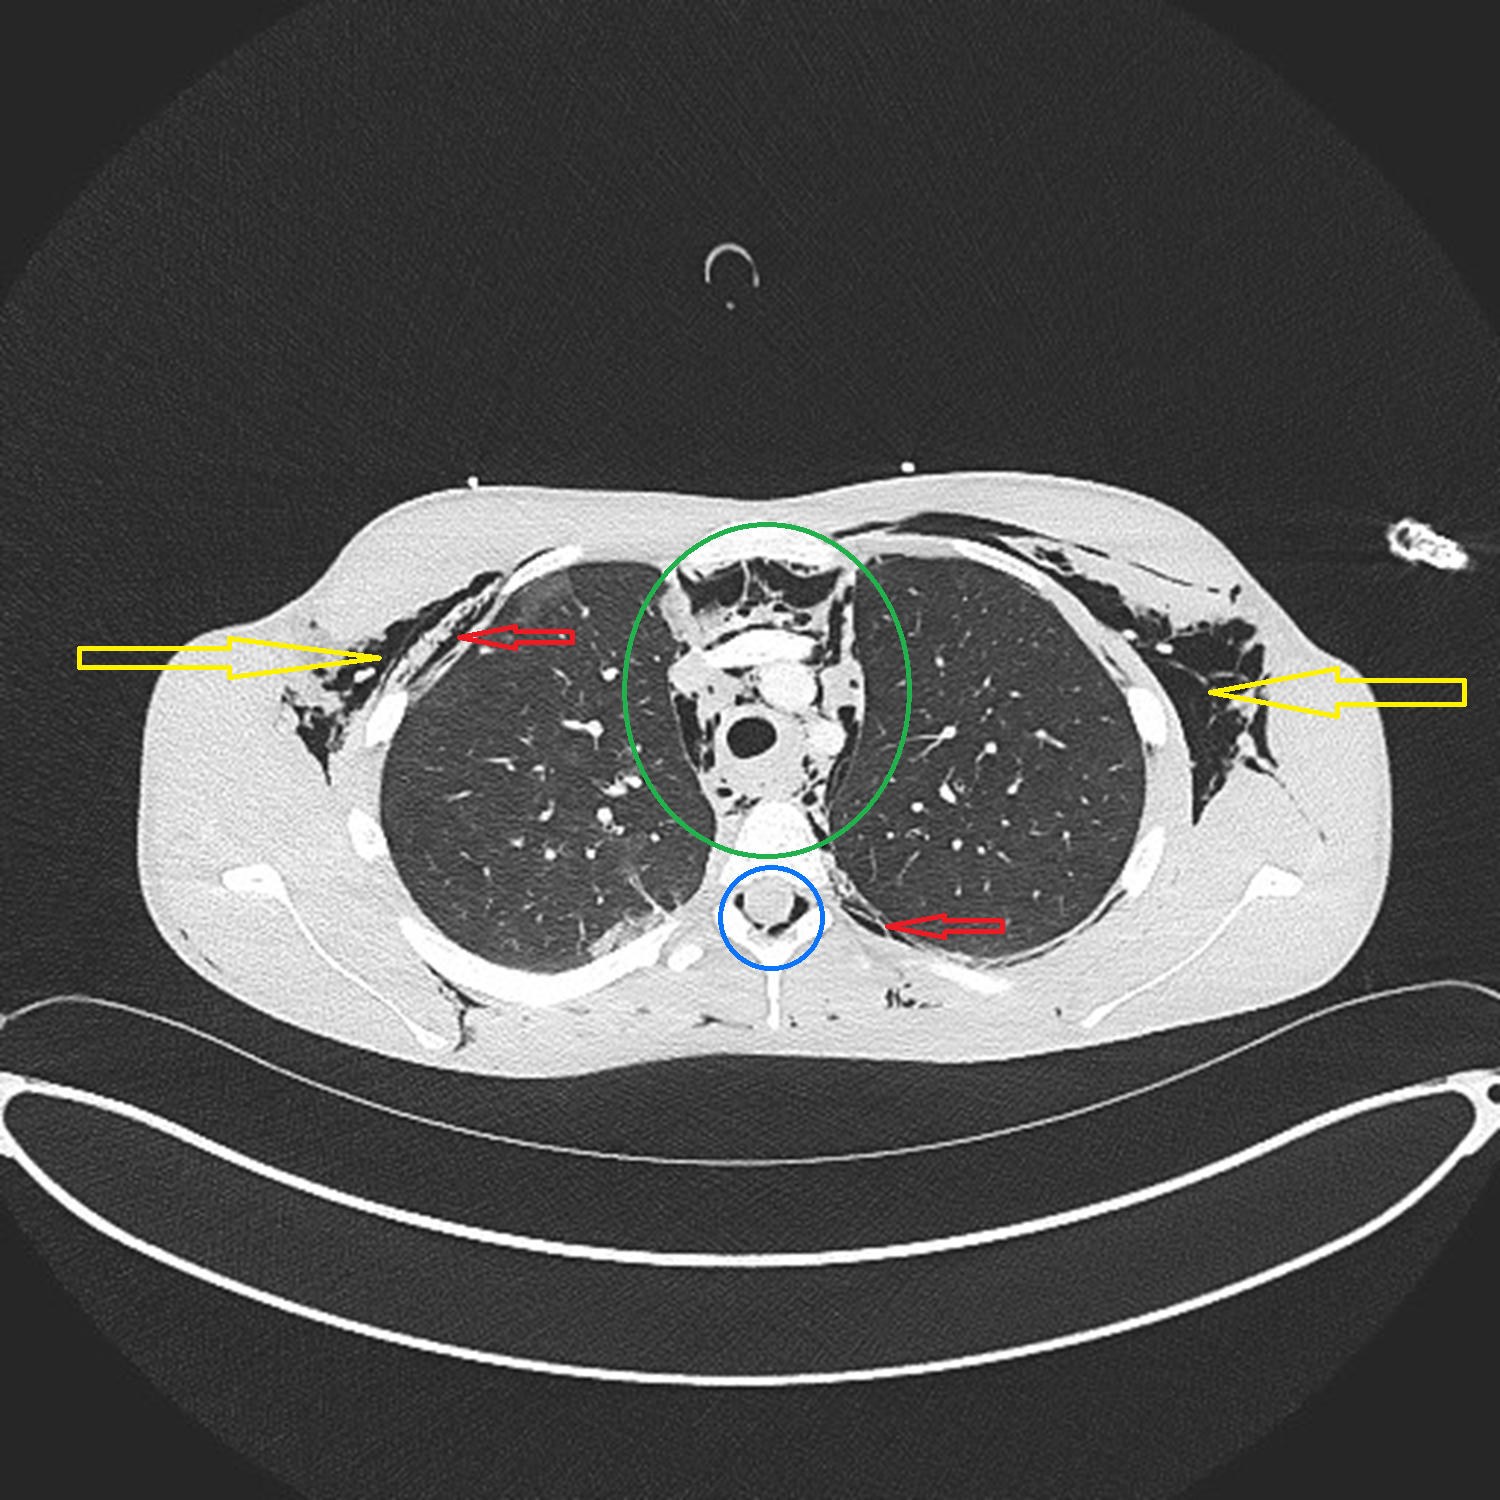

A CT scan allowed medics to diagnose “air leak syndrome”, in which pockets of gas or air had collected in parts of the body including the spinal canal, between the lungs, and under the skin.

EVIDENCE: A CT scan showed where pockets of gas or air had collected